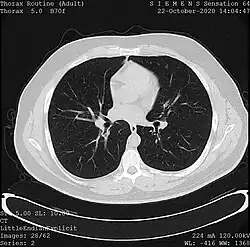

- X-ray computed tomography (CT), or Computed Axial Tomography (CAT) scan, is a helical tomography technique (latest generation), which traditionally produces a 2D image of the structures in a thin section of the body. In CT, a beam of X-rays spins around an object being examined and is picked up by sensitive radiation detectors after having penetrated the object from multiple angles. A computer then analyses the information received from the scanner's detectors and constructs a detailed image of the object and its contents using the mathematical principles laid out in the Radon transform. It has a greater ionizing radiation dose burden than projection radiography; repeated scans must be limited to avoid health effects. CT is based on the same principles as X-ray projections but in this case, the patient is enclosed in a surrounding ring of detectors assigned with 500–1000 scintillation detectors[20] (fourth-generation X-ray CT scanner geometry). Previously in older generation scanners, the X-ray beam was paired by a translating source and detector. Computed tomography has almost completely replaced focal plane tomography in X-ray tomography imaging.